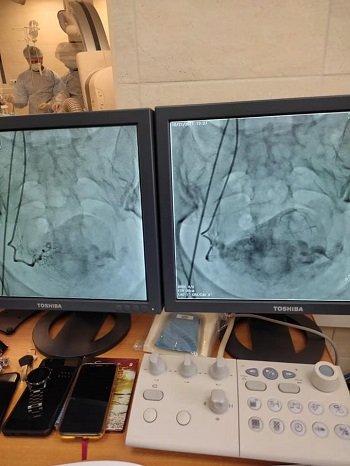

Вперше у Херсонській області з'явилась унікальна можливість відновити кровоток у будь-який артерії організму. 21 жовтня 2021 року було проведено перші 3 операції на серці та головному мозку. Про це повідомив на власній сторінці Фейсбук головний лікар Херсонської обласної клінічної лікарні Віктор Короленко. «В обласній клінічній лікарні відкрився центр інтервенційної радіології.

Це структурне відділення серцево-судинної хірургії, що дозволяє робити весь спектр ендоваскулярних втручань. Тобто, проведення мало травматичних, діагностичних і лікувально- оперативних втручань за допомогою спеціальних мініатюрних катетерних інструментів. Які вводяться через точковий прокол під місцевим знеболюючим без розрізів та наркозу. Ця можливість з'явилась завдяки придбаному стаціонарному ангіографу. Це універсальний апарат, який вирішує величезний блок кардіохірургічних проблем незалежно від місця їх розташування (головний мозок, сердце або нижні кінцівки) Наприклад:

- постановка стендів в артеріях головного мозку для профілактики інсультів;

- планова коронарографія;

- відновлення прохідності судин при інфарктах (стентування);

- лікування вроджених вад серця; відновлення кровотоку нижніх кінцівок;

- відновлення кровотоку в артеріях головного мозку при гострих інсультах та інше», - йдеться в повідомленні.